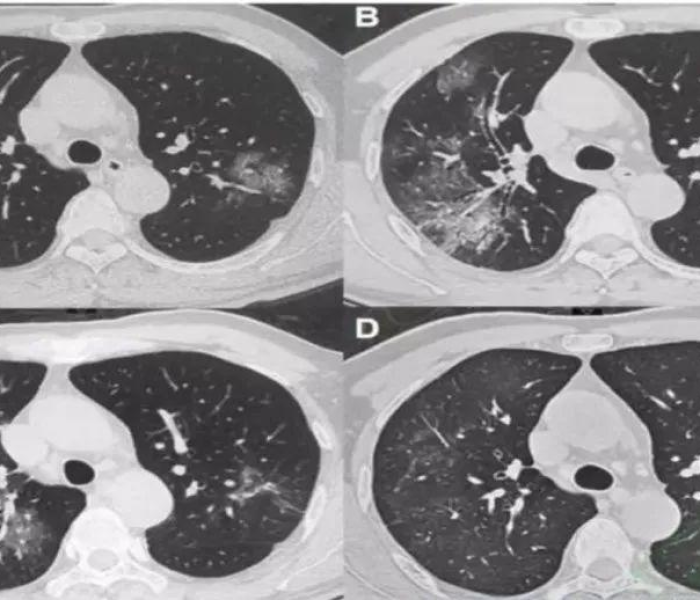

无锡疫情 确诊病例

无锡疫情 疫情防控